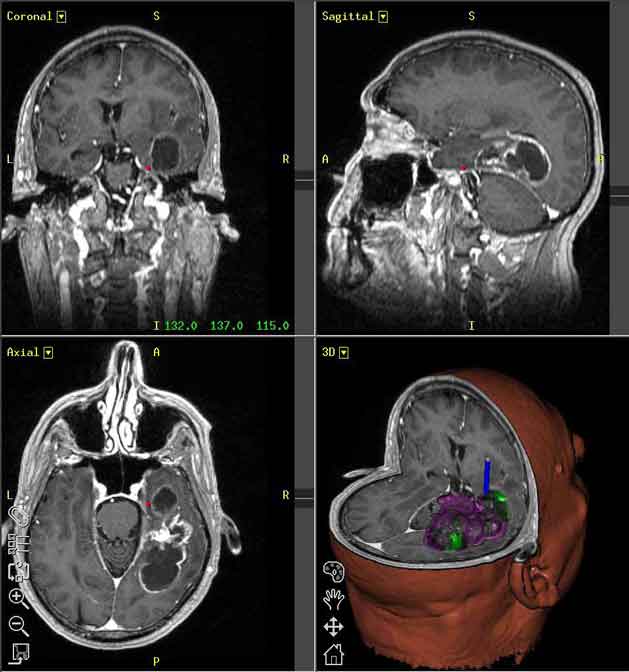

Ricercatori della Facolta’ di Medicina e Chirurgia ”A. Gemelli” dell’Universita’ Cattolica di Roma hanno tracciato l’identikit biomolecolare del piu’ aggressivo tumore cerebrale, il glioblastoma multiforme e del tessuto che si trova intorno al tumore (peritumorale). Questo tessuto, apparentemente normale alla risonanza magnetica, e’ la sede della recidiva del tumore nel 90% dei casi.   Proprio per questo al suo interno vanno cercate le chiavi per sconfiggere il glioblastoma, che appare aggressivo e variegato. In particolare, la caratterizzazione genica del tessuto peritumorale ha dato interessanti informazioni sui principali geni e sulle proteine, che giocano un ruolo fondamentale nella progressione del tumore e potrebbero rappresentare la base per la messa a punto di una terapia personalizzata. La determinazione del profilo genico, condotta grazie ai finanziamenti ottenuti nell’ambito di un progetto FIRB coordinato da Giulio Maira, Direttore dell’Istituto di Neurochirurgia dell’Universita’ Cattolica, e’ derivata dalla collaborazione tra genetisti, biologi molecolari, istologi e anatomopatologi e si e’ tradotta in una recente pubblicazione sulla rivista Plos One, firmata tra gli altri in qualita’ di primo autore da Annunziato Mangiola, ricercatore di Neurochirurgia, e da Gigliola Sica, Direttore dell’Istituto di Istologia ed Embriologia della Cattolica di Roma. Il glioblastoma multiforme e’ un tumore del cervello che colpisce circa 8 persone ogni centomila abitanti con una sopravvivenza media di 13-14 mesi.

Il problema principale di questo tipo di cancro e’ che inevitabilmente recidiva dopo essere stato rimosso chirurgicamente e trattato con radio e chemioterapia. Negli ultimi anni si e’ via via compreso che il tessuto cerebrale limitrofo al tumore e’ alterato anche in assenza di infiltrazione da parte di cellule tumorali. Quest’ultimo non era mai stato caratterizzato nel dettaglio finora da un punto di vista genetico e molecolare. Poiche’ il tessuto peritumorale e’ sede del 90% delle recidive ci si e’ anche chiesto se in esso si annidassero delle staminali del cancro, fonte di nuovi tumori. I ricercatori dell’Universita’ Cattolica hanno dimostrato che il tessuto peritumorale e’ sede di profonde alterazioni di tipo biochimico e funzionale e puo’ presentare cellule staminali putative, anche se all’esame istologico e’ apparentemente normale. Inoltre essi hanno messo a confronto il tumore ed il tessuto peritumorale senza segni di chiara infiltrazione neoplastica con tessuto normale prelevato da soggetti operati a livello cerebrale per patologie non tumorali. ”E’ emerso che il tessuto peritumorale ha un profilo di espressione genica (cioe’ un pattern di geni ”on” ed ”off”) molto diverso dal tessuto sano – spiegano Sica e Mangiola -. Quindici geni tra quelli valutati funzionano troppo (over-espressi), oltre 40 funzionano troppo poco (sotto-espressi) rispetto al tessuto nervoso sano, ma il profilo genico globale presenta notevoli similitudini con quello del glioblastoma. Questo e’ il segno che nell’area peritumorale vi e’ una situazione simile a una precancerosi”. La determinazione dell’espressione genica del tessuto peritumorale nel singolo paziente potrebbe condurre alla messa a punto di terapie mirate per impedire che il tumore si ripresenti.